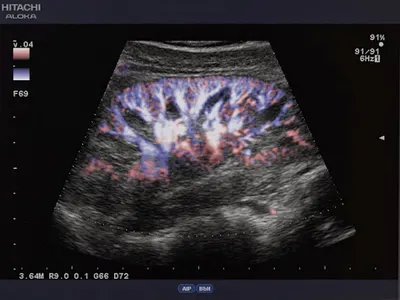

W Kaliszu, przy ulicy Majkowskiej 13A, znajduje się ISPL Zaremba P. – indywidualna specjalistyczna praktyka lekarska specjalizująca się w chirurgii. Prowadzona przez doświadczonego chirurga, placówka oferuje zabiegi operacyjne, w tym laparoskopowe usuwanie pęcherzyka żółciowego. Lokalizacja w sercu miasta ułatwia pacjentom dostęp do profesjonalnej opieki medycznej bez konieczności wyjazdów poza region. Praktyka cieszy się doskonałą opinią wśród pacjentów, osiągając ocenę 5.0/5 na Google na podstawie czterech recenzji. Klienci podkreślają brak komplikacji po zabiegach resekcji pęcherzyka żółciowego oraz precyzyjne wyjaśnienia procedur krok po kroku. Jeden z nich chwali: „Pan doktor to przecudowny człowiek, prawdziwy lekarz z powołania, laparoskopia przebiegła profesjonalnie”. Inni polecają doktora Piotra za super podejście i skuteczność. Wybór ISPL Zaremba P. to gwarancia rzetelnej obsługi w warunkach kaliskiego rynku medycznego. Pacjenci doceniają nie tylko wyniki operacji, ale i ludzkie podejście lekarza, co buduje zaufanie w lokalnej społeczności. (Liczba słów: 178)

- Bezkomplikacyjne zabiegi resekcji pęcherzyka żółciowego

- Profesjonalny przebieg operacji laparoskopowej

Idealny dla pacjentów wymagających laparoskopowej resekcji pęcherzyka żółciowego, szukających empatycznego i profesjonalnego chirurga.